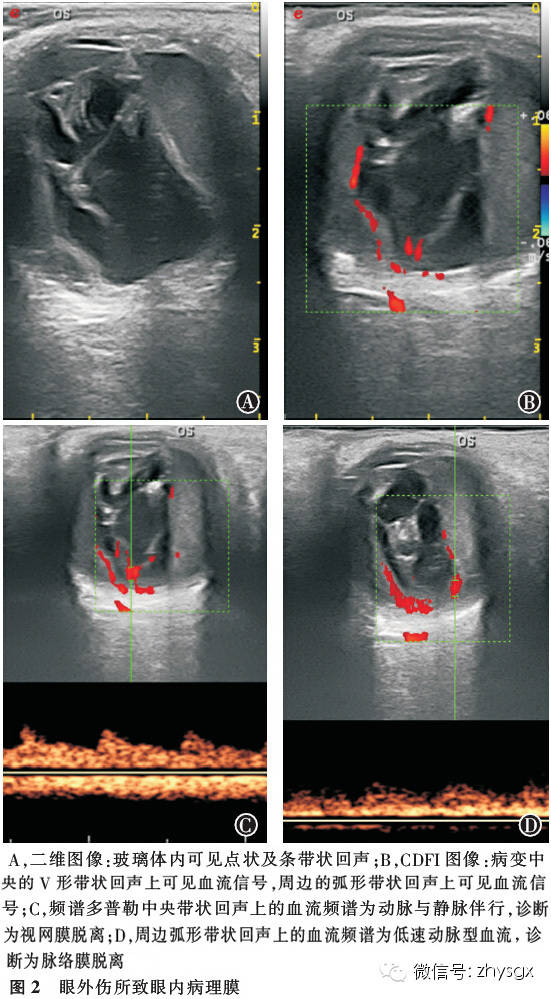

【摘要】 目的 探讨眼外伤所致眼内病理膜的彩色多普勒超声诊断特点。方法 回顾性病例研究。选择2013年1-12月因眼外伤行眼部彩色多普勒超声检查的患者1 156例(1 162眼),对其彩色多普勒超声诊断特点进行总结和分析,部分病例经手术确定诊断,判断彩色多普勒超声诊断的准确性。结果 1 156例(1 162眼)的超声诊断包括玻璃体积血(1 071 眼)、眼内炎(78眼)、玻璃体后脱离(624眼)、视网膜脱离(521眼)、脉络膜脱离(221眼)、脉络膜上腔积血(117眼)等。眼外伤所致的玻璃体内膜状病变的彩色多普勒超声诊断特点为单一疾病表现典型,但多数患者存在2种或2种以上病变。应用彩色多普勒超声检查,在参考二维超声检查结果的同时,根据视网膜、脉络膜的血供特点,可以在错综复杂的眼内条带状回声中分辨出脱离的视网膜和脉络膜,为手术和治疗提供可靠的依据。本组部分病例经手术治疗。总体超声诊断与临床和手术诊断的符合率为99.1%。结论 应用彩色多普勒超声检查眼外伤所致玻璃体内膜状病变是一种经济、简便、无创、可重复性好的诊断方法,根据视网膜和脉络膜的血流特征分析方法,可以提高超声诊断的准确性。

【Abstract】 Objective To investigate thecharacteristics of damage to intraocular membranes from ocular trauma usingcolor Doppler flow imaging (CDFI) for diagnosis. Methods Weretrospectively studied 1 162 eyes of 1 156 patients who sustained ocularinjuries from January 2013 to December 2013. CDFI was used to detect damage toocular membranes. The surgical diagnosis was also reviewed. Results Among 1 162 eyes of 1 156 patients, vitreous hemorrhage presented in 1 071 eyes, endophthalmitis presented in 78 eyes, andposterior vitreous detachment presented in 624 eyes. There were 521, 221 and 117 eyes with retinal detachment,choroidal detachment and choroidal hemorrhage,respectively. While trauma to intraocular membranes is typically associatedwith a single injury identified with CDFI, most of thepatients suffered from various injuries. Color Doppler flow imaging detectedthe damaged tissues with 2D images. Moreover, theimaging can analyze the retina and choroid blood flow to help distinguishretinal or choroidal detachment. In this study, 99.1%of the ultrasound diagnoses matched the clinical and surgical diagnoses.Conclusion Color Doppler flow imaging isan economical and simple way to detect intraocular membrane injury from oculartrauma. It is also noninvasive and repeatable. The use of retinal and choroidalblood flow analysis can increase the detection rate of intraocular membraneinjury from ocular trauma.